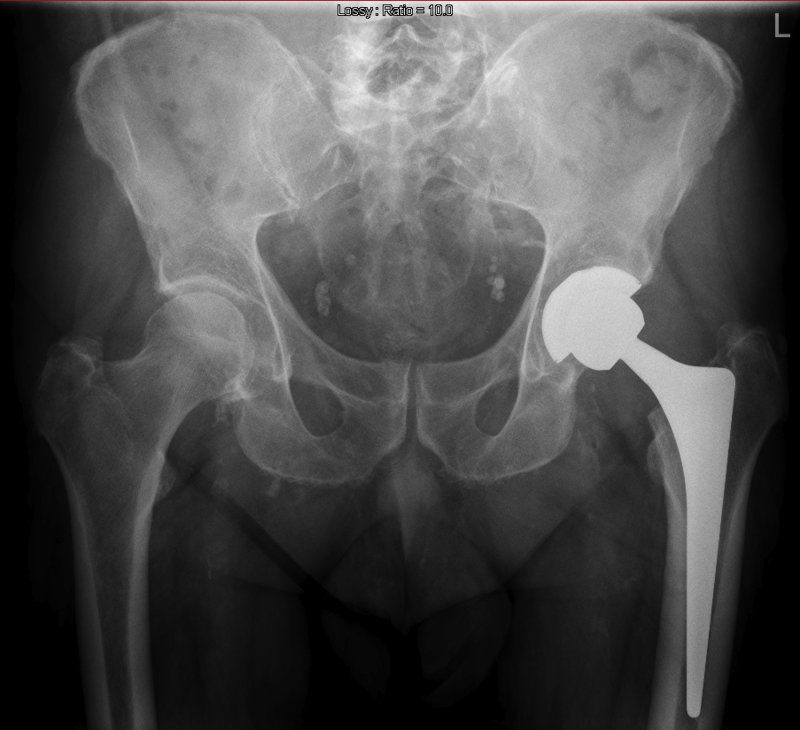

Los autores revisaron ensayos clínicos en los que, al azar, los participantes habían ingerido vitamina D o calcio, solos o combinados, un placebo o ningún tratamiento. Todos los estudios se habían concentrado en el riesgo de fractura de cadera, columna u otros huesos.

La falta de una asociación entre el consumo de calcio o vitamina D y el riesgo de fractura se observó en ambos sexos, sin importar la dosis de los suplementos o fracturas previas, según publica el equipo en JAMA.